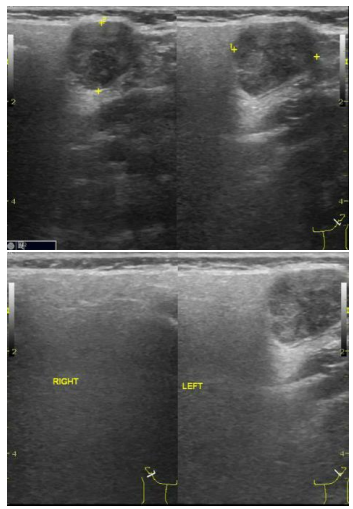

Você realiza o exame ultrassonográfico de glândulas

salivares de uma paciente do sexo feminino de 30 anos e

encontra a seguinte imagem. Assinale a alternativa

correta.